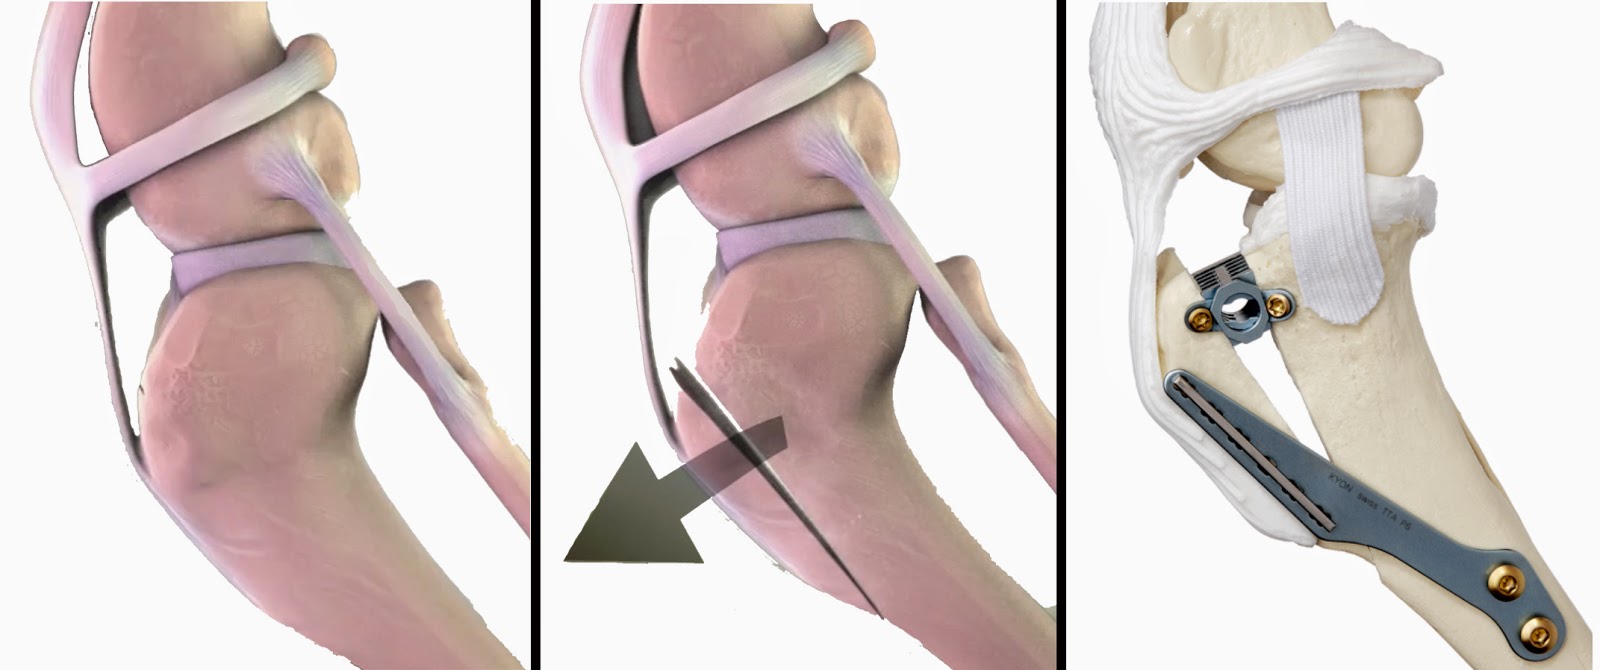

TTA - Tibial Tuberosity Advancement

La TTA (Avanzamento della Tuberosità Tibiale) è una tecnica relativamente nuova per il trattamento della rottura del legamento crociato craniale. La tecnica è stata fortemente influenzata da considerazioni biomeccaniche ed ha, come la TPLO, lo scopo di annullare le forze che agiscono sul legamento crociato craniale del ginocchio tramite un riassetto della conformazione dello stesso.

La tecnica è meno invasiva delle procedure alternative, minimizza i tempi chirurgici e preserva il range of motion articolare. Il recupero dal punto di vista clinico è più rapido rispetto alle altre tecniche.

La TTA si inserisce nel panorama mondiale come una tecnica in grado di modificare la geometria del ginocchio per trattare la rottura del legamento crociato craniale, quindi si pone come obiettivo non quello di ricostruire il legamento lesionato ma bensì quello di modificare la biomeccanica del ginocchio.